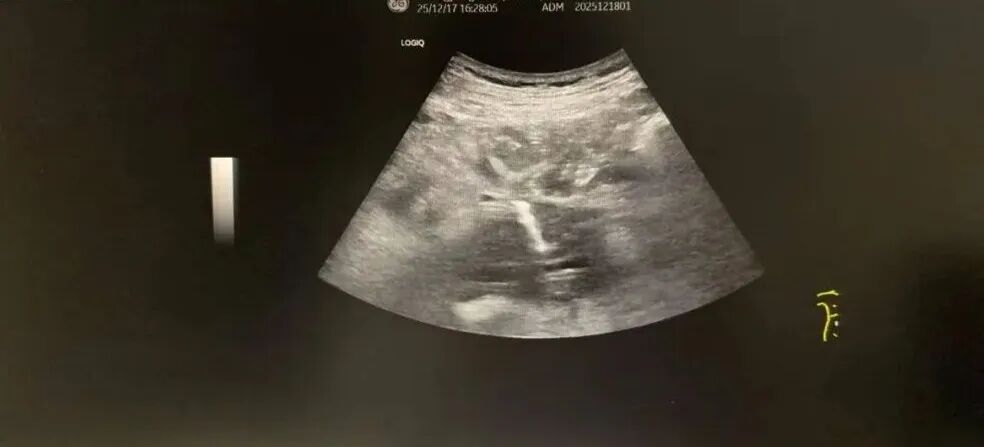

包块内穿刺针及血流图

手术过程中,黄光亮教授全程主导操作,团队成员密切配合。超声探头下,病灶与血管搏动清晰可辨,黄光亮凭借毫米级的精准操控,稳稳避开肠管与核心血管,将细针精准刺入腹膜后肿块,成功获取3条高质量组织标本。整个手术安全顺利,患者术后无明显不适,次日即可正常活动。